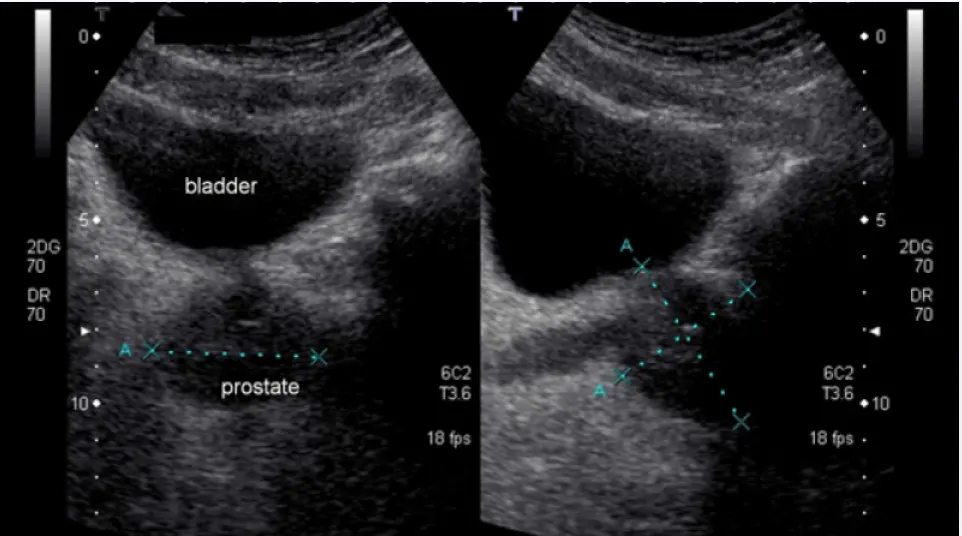

التهاب البروستات مرض شائع يمكن أن يكون له تأثير كبير على صحة الرجال. في هذا المقال سأتحدث عن تجربتي في التعامل مع التهاب البروستاتا وكيف ساعدتني الحبوب الطبيعية في التخلص من هذا المرض دون آثار جانبية. إذا كنت تبحث عن علاجات بديلة لالتهاب البروستاتا ، فقد تكون تجربتي مفيدة لك.

اولا ، التهاب البروستات لدي ليس مزمنًا. اصبت بالبرد أثناء الصيد ، في البداية اعتقدت أنني مصاب بالتهاب في المسالك البولية ، لأنني كثيرًا ما أجري. ثم كان هناك ألم في الفخذ ، وعدم الراحة أثناء التبول . باختصار ، ركضت إلى الطبيب ، قاموا بفحصي وجعلوني سعيدًا ، يقولون ، أنت ، يا صديقي ، مصاب بالتهاب البروستاتا. هنا ، بالطبع ، تومضت حياتي الجنسية بالكامل أمام عيني ، لقد ظننت انه لن استطيع ممارسة الجنس بعد هذا ، لكن الطبيب قال أننا سنتعالج.